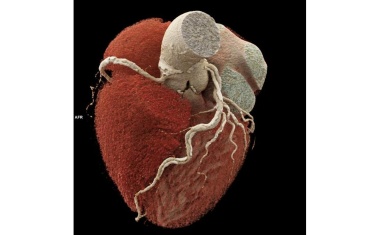

Zur Abklärung eines Verdachts auf koronare Herzerkrankung (KHK) soll die Computertomographie der Herzkranzgefäße (CCTA) ab sofort in die Kassenleistungen eingeschlossen werden.

Die Deutsche Röntgengesellschaft und der Berufsverband der Deutschen Radiologen begrüßen die Aufnahme der Computertomografie des Herzens in die Gesundheitsversorgung gesetzlich Versicherter.

Ultra-hochauflösende volldigitale Photon-Counting-Computertomografie ermöglicht bei Hochrisikopatient*innen erstmals eine präzise nicht-invasive Untersuchung von Herzkrankheiten.